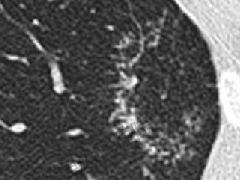

2.病变周围GGO,边界清楚或稍模糊。圆圈征、草帽征、树上蘑菇征等。

8、斑片常伴有结节,边缘清楚GGO或欠清楚。